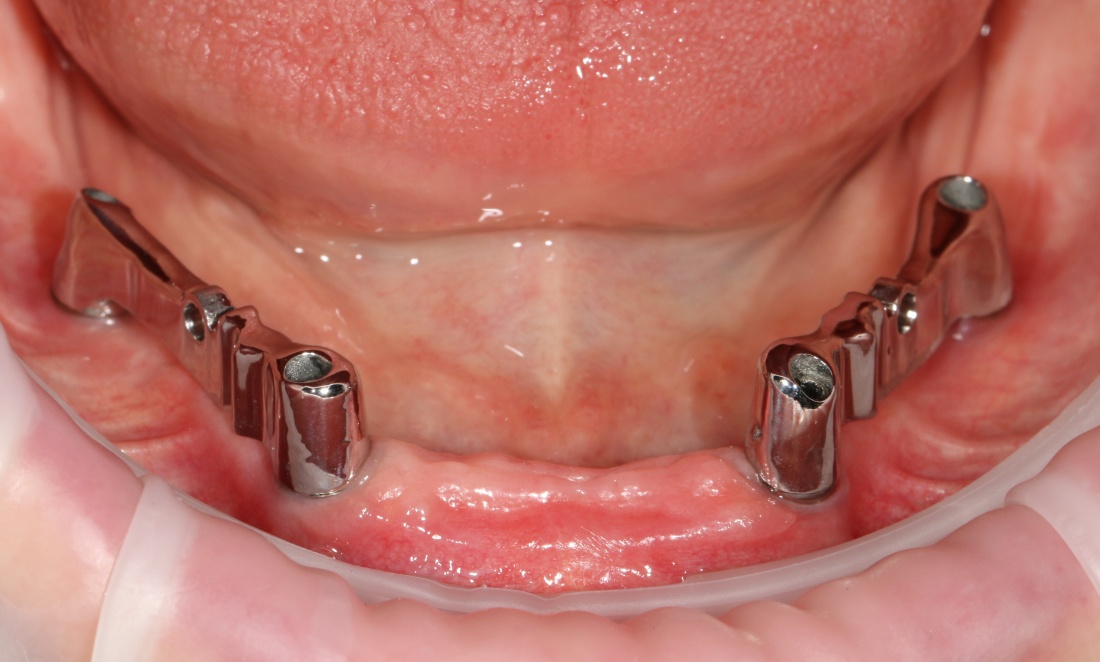

Рекомендации по установке имплантов. Для всех. Часть V.